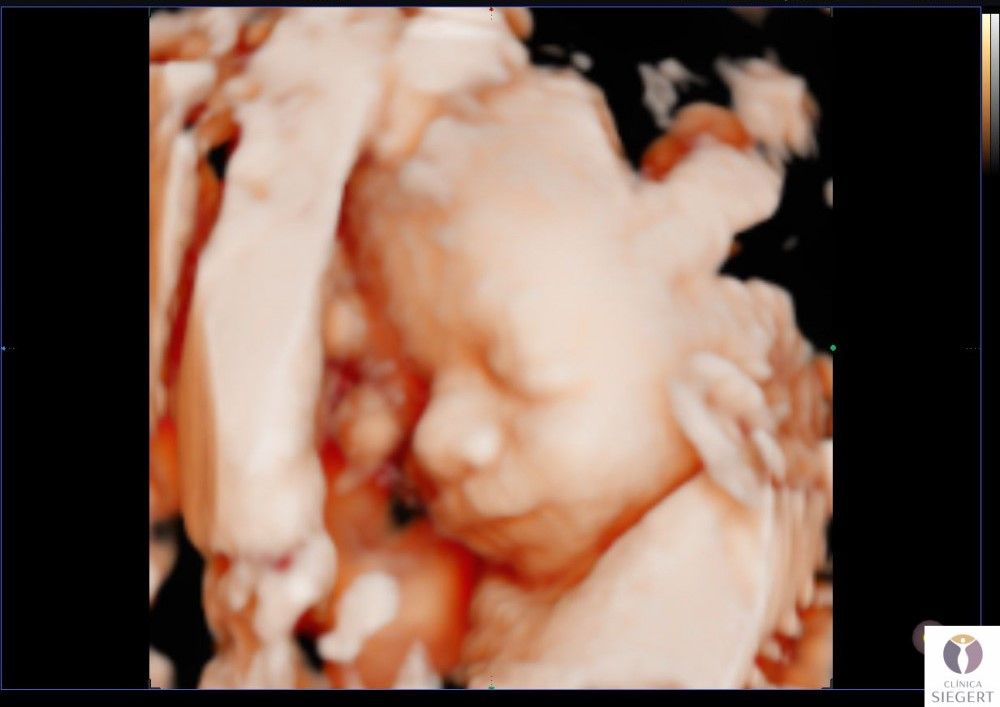

Nuevo ecógrafo de última generación con la mejor imagen 3D 4D 5D (edición en vivo: HD LIVE). ¡CONOCE A TU BEBÉ ANTES DE NACER! En Clínica Siegert, en Ibi